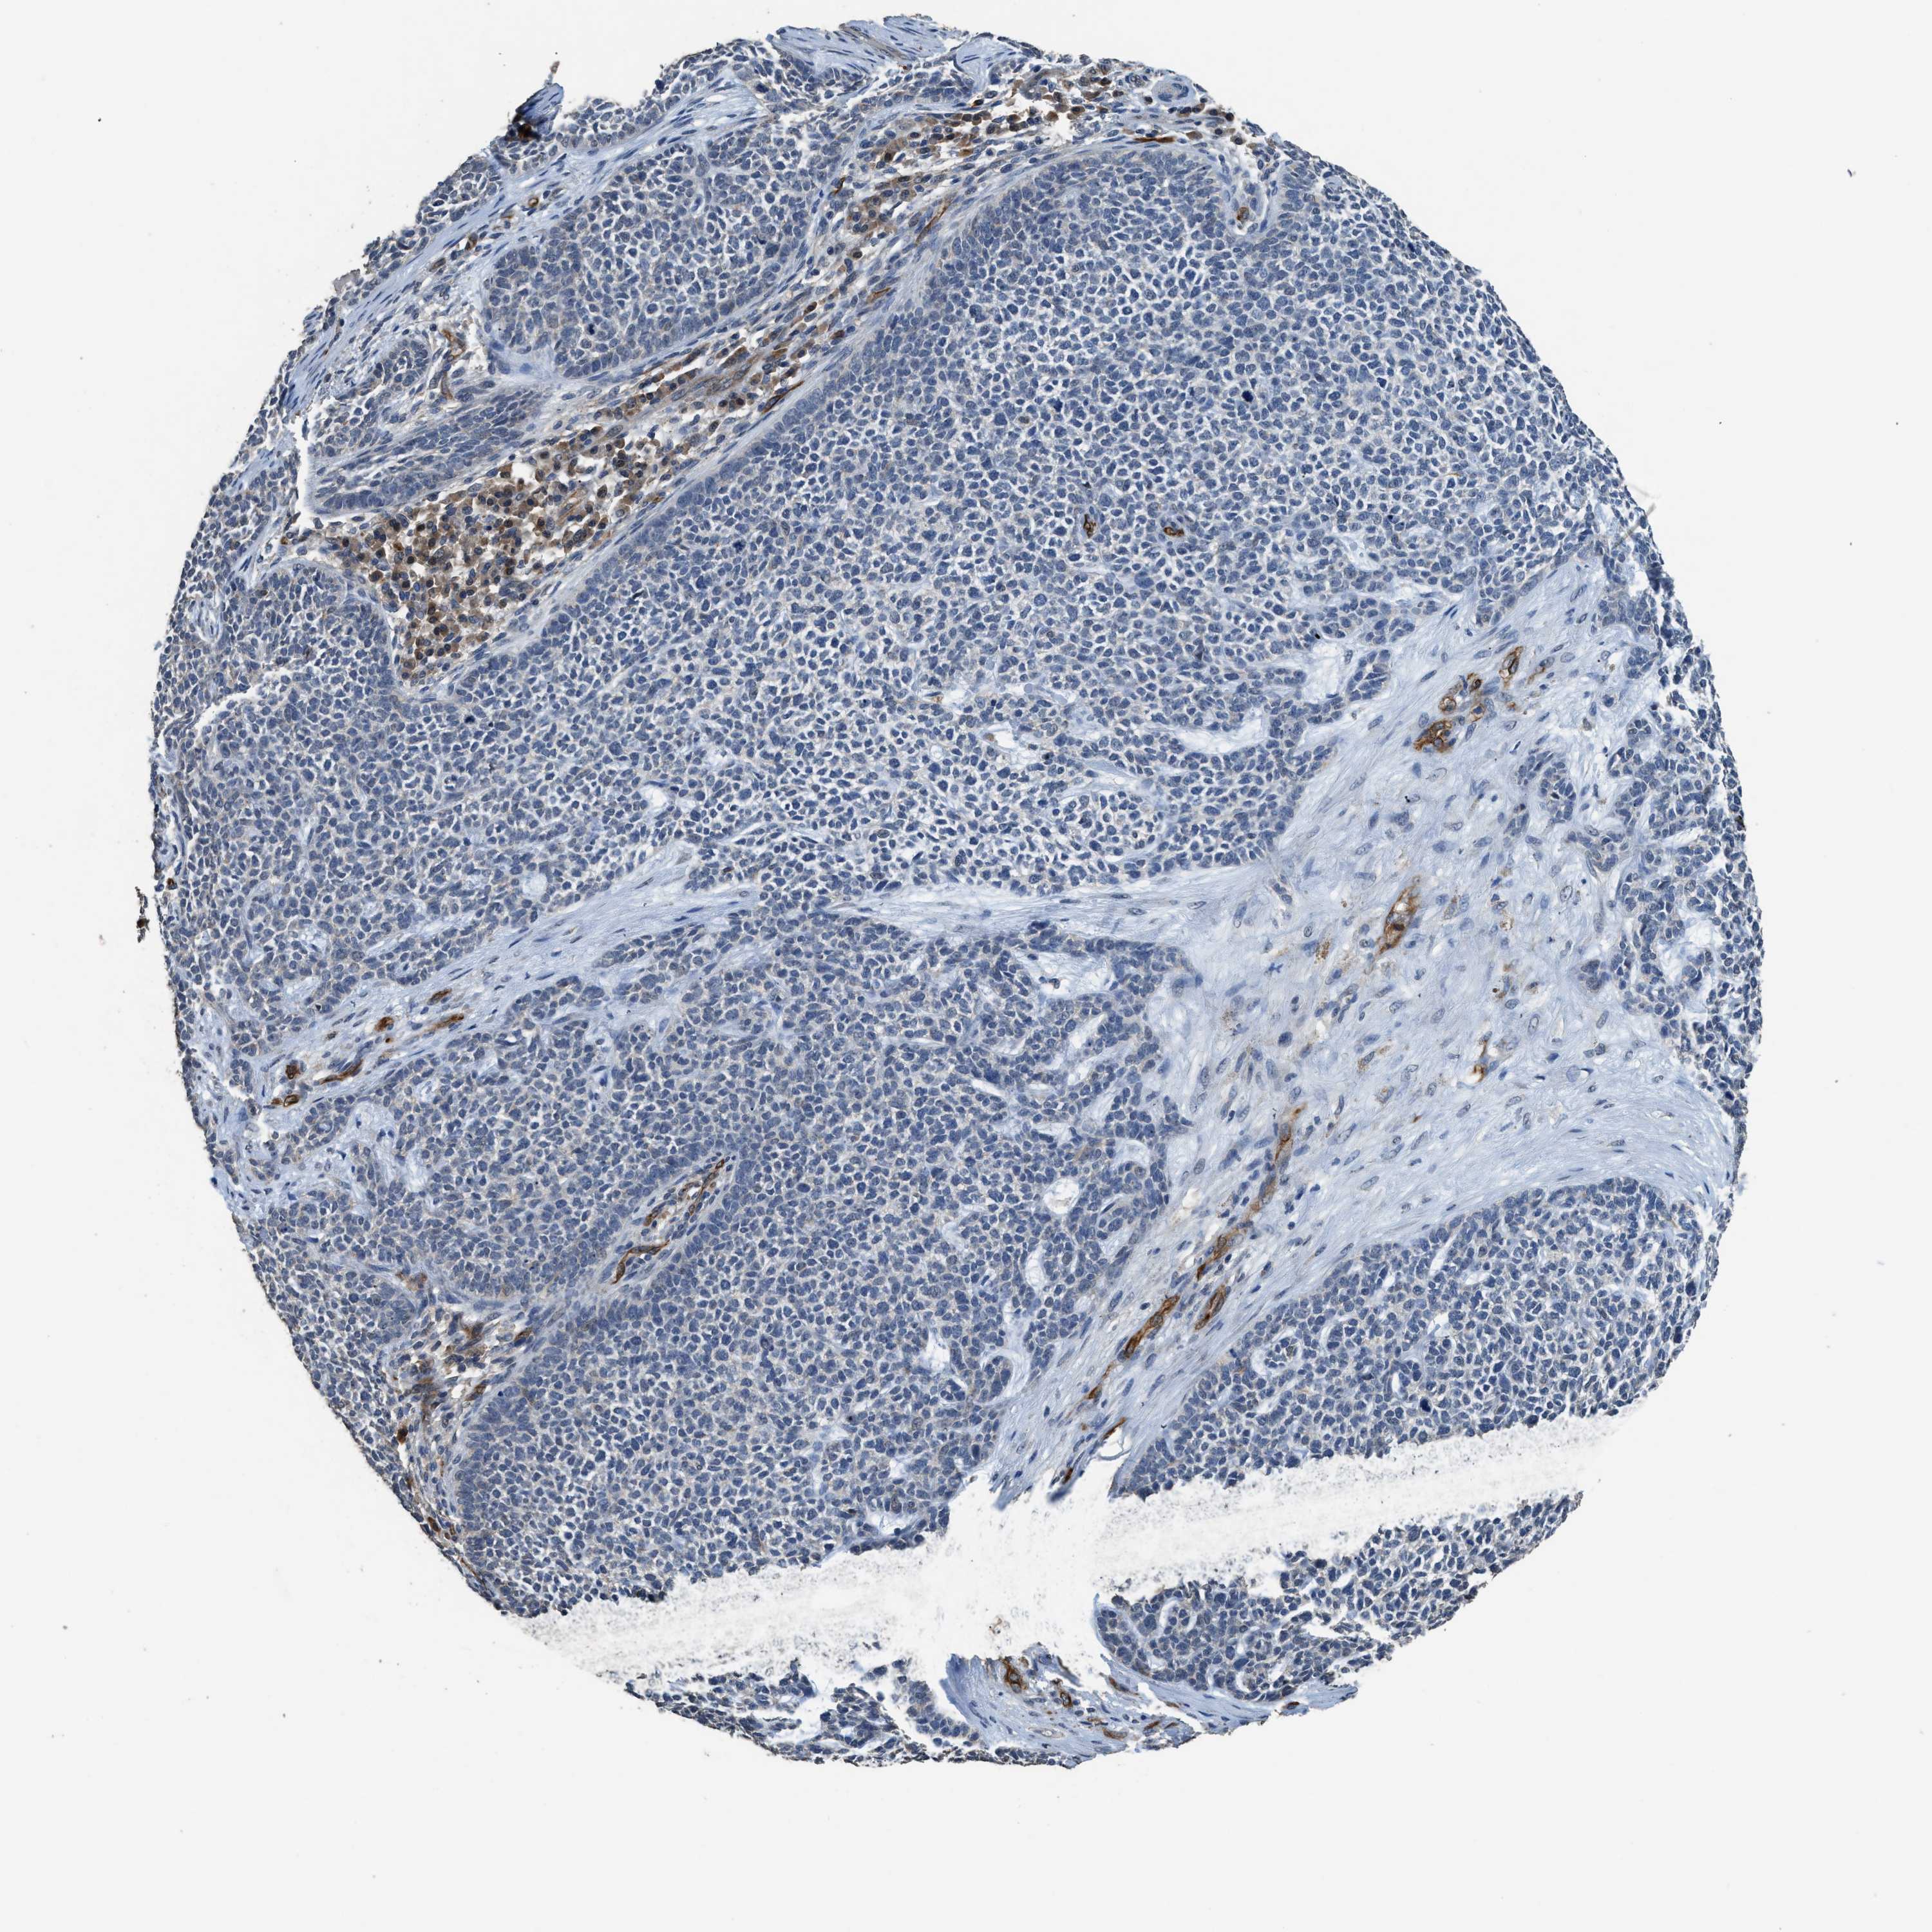

SKIN CANCER - Protein expressioni

A mouse-over function shows sample information and annotation data. Click on an image to view it in a full screen mode. Samples can be filtered based on level of antibody staining by selecting one or several of the following categories: high, medium, low and not detected. The assay and annotation is described here.

Antibody staining in the annotated cell types in the current human tissue is reported as not detected, low, medium, or high, based on conventional immunohistochemistry profiling in selected tissues. This score is based on the combination of the staining intensity and fraction of stained cells.

Each image is clickable and will lead to virtual microscopy that enables deeper exploration of all samples and also displays staining intensity scores, fraction scores and subcellular localization as well as patient and tissue information for each sample.

Antibody HPA040066

Antibody HPA044200

Antibody CAB017192

Basal cell carcinoma

Squamous cell carcinoma, NOS